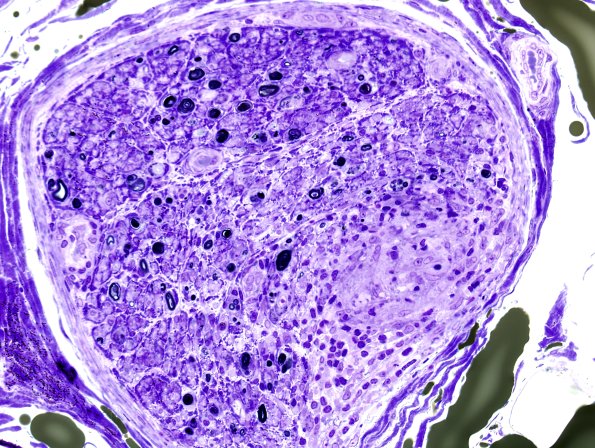

Washington University Experience | PERIPHERAL NEUROPATHY | 9A SARCOID | 1E1D Sarcoid, no bugs (Case 1) Plastic 6

Plastic sections show severe loss of both large and small myelinated axons (large>small) as well as actively degenerating axons. There are large myelinated axons with myelin sheaths which are thin for caliber and focal regenerative clusters are present. There is a variable amount of perineurial involvement. (Plastic sections)